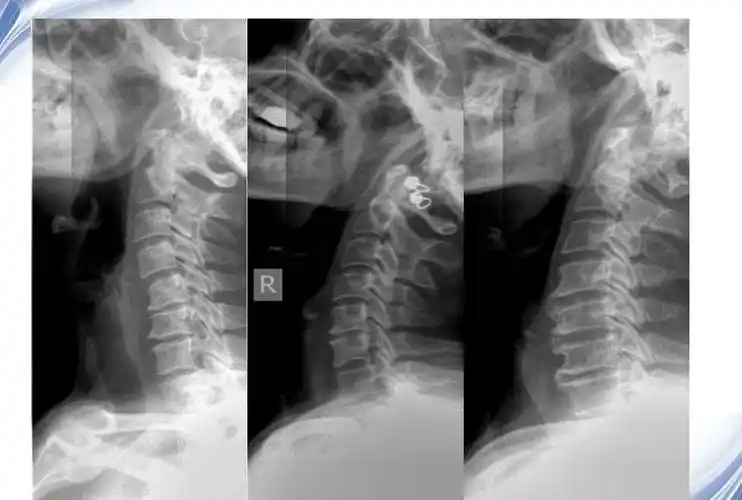

颈椎x线诊断的内容及其解读